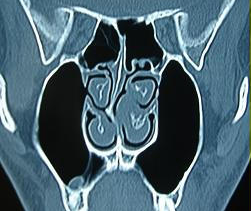

鼻中隔偏曲是指鼻中隔發生偏向一側或兩側、造成鼻腔功能障礙的一種常見的鼻部疾病。鼻中隔偏曲的主要癥狀包括交替性或持續性鼻塞、反射性頭痛、鼻出血、流膿涕以及鄰近器官癥狀等。這些都嚴重影響人的生活和工作,需要及時進行治療,可自行選擇上述偏方lf或者其他正規治療方法。

圖:鼻中隔偏曲CT